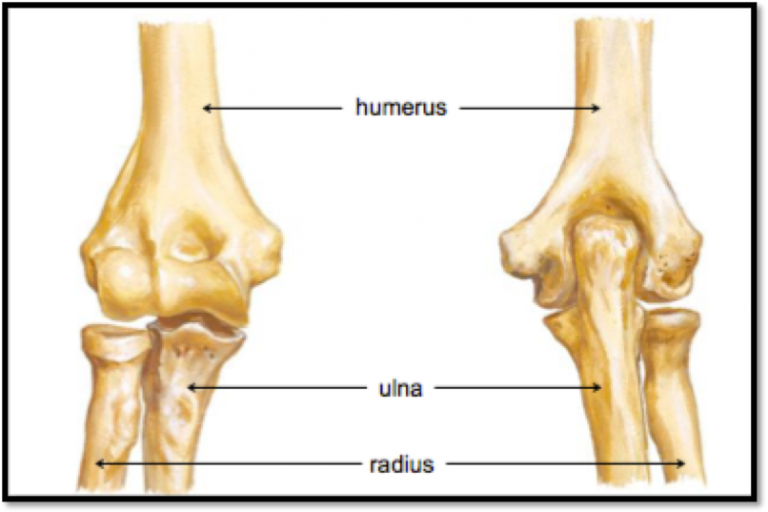

The elbow joint is formed by 3 bones- one arm-bone (Humerus) and two forearm bones (Radius, ulna). Like other joints the two bones are connected by ligaments and surrounded by muscles.